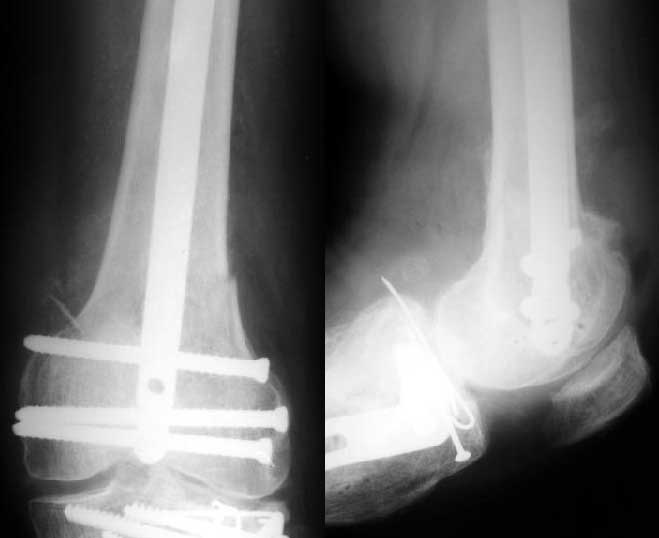

Отправитель: V. M. Iyer 28 Декабрь 2003, 20:25

1

Alex>> Than in the presented case?

I do not see the proximal bolts; I presume they must be at he trochanter level. In a supracondylar nail you are able to see both side bolts in one picture. ( Enclosure)